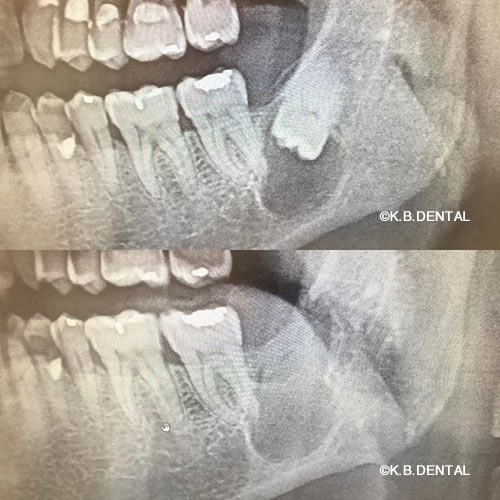

珍しい症例で、歯を含む膿胞のケースです。この方は、一般的な親知らず付近の痛みで来院されましたが、親知らず付近の顎骨腫瘍の場合、神経や血管のの近くに出来て、激痛や顎のシビレ、膿が出る症状が伴うこともあります。このような親知らずが全く逆さまに埋まっている場合、他の病院で検査していたとしても抜けないということで放置しているケースも多々あります。

料金

静脈内鎮静法による麻酔代込み:約15~20万円(保険適用外)